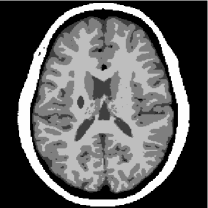

For the numerical studies we set up an artificial brain phantom (see Figure 5) with a size of x pixels using data from BrainWeb [15], which features the typical challenges of a joint reconstruction.

![]() |

\begin{overpic}[height=108.405pt]{figure5a_cbar} \put(0.75,91.0){\small$10$} \put(2.75,3.0){\color[rgb]{1,1,1}{$0$}} \end{overpic} | ![]() |

\begin{overpic}[height=108.405pt]{figure5a_cbar} \put(2.75,91.0){\small$1$} \put(2.75,3.0){\color[rgb]{1,1,1}{$0$}} \end{overpic} | ![]() |

| (a) PET phantom | (b) MRI phantom | (c) PET data |

First of all, both phantoms feature the exact same location of edges everywhere except for the two artificially added lesions in the upper right part of the PET image and the left part of the MR image. Both have been added to illustrate a common joint reconstruction problem, namely the introduction of artifacts, i.e. features not present in one of the images that are transferred artificially to the other. While the locations of the edges are equal, the jumps across the edges are not, meaning that we e.g. have a “step up” from gray matter to white matter in the MR image, while we have a “step down” in the PET image. Furthermore, we point out the different range of image intensities. This imposes the issue of locally different gradient heights, which cannot be dealt with thoroughly by a global scaling of the data. Summing up we find the following features:

-

•

Equal edge locations (except for two lesions),

Equal and different edge orientations,

Different height of jumps across edges,

Different scale.